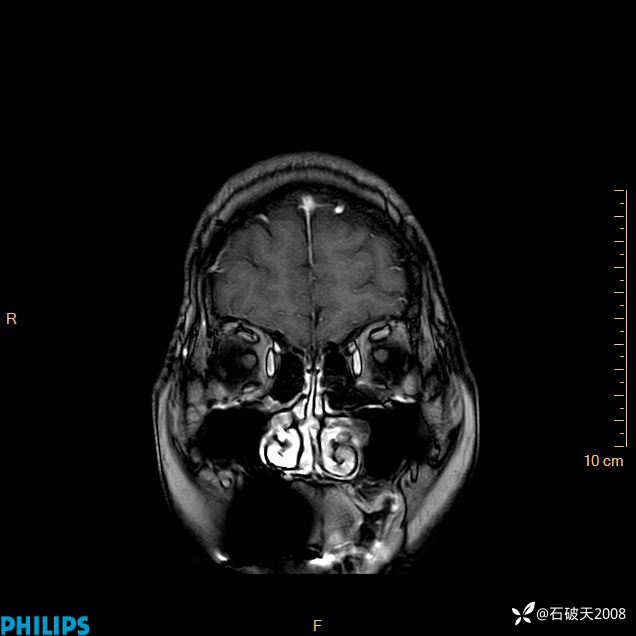

增强冠状位